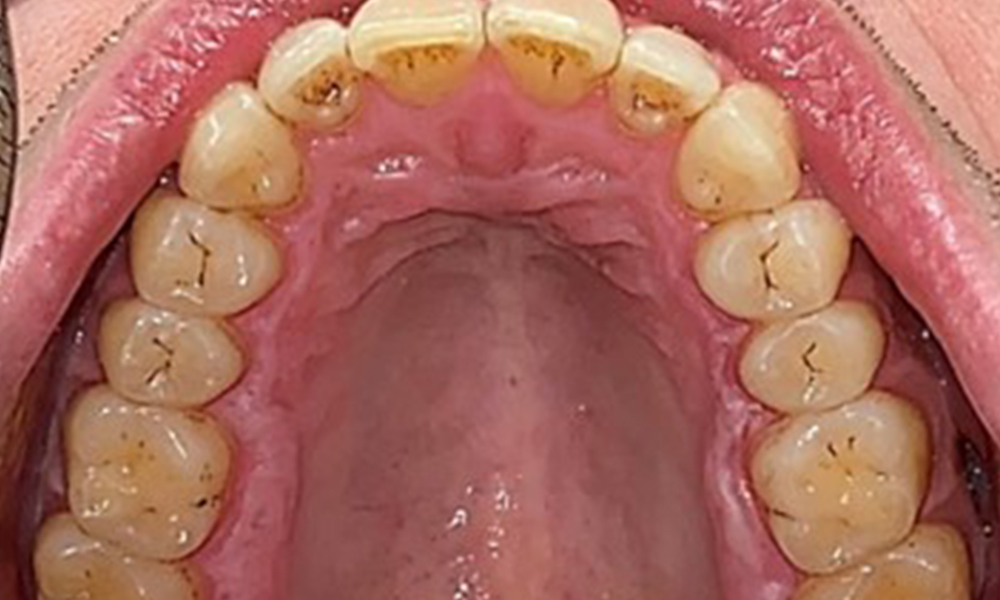

Occlusal view of the maxilla.

Fig. 3: Occlusal view of the maxilla, © Dr R. Krapf

Dental findings

The patient has full dentition with a total of 28 teeth. There were noteworthy erosions and attritions. (Fig. 4, Fig. 5). Due to bruxism, the patient has been wearing a splint with an adjusted bite block at night for many years. The erosions were caused by long-term consumption of isotonic beverages. No periodontal bone loss or active caries were observed.